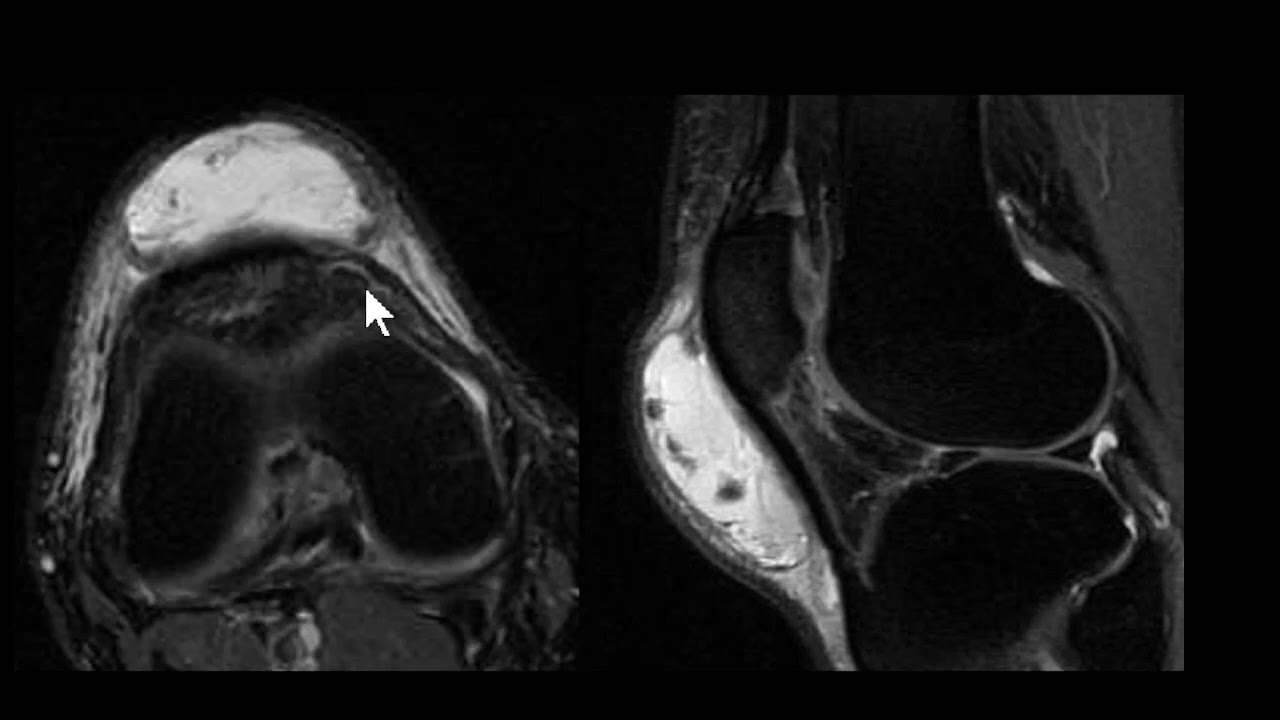

saudações vamos aqui a Mais Um Caso o contexto clínico é de um paciente que sofreu uma torção aguda do tornozelo e temos essa ressonância magnética aqui um axial DP com saturação de gordura e vamos observar aqui aqui é a fíbula corte aqui no plano axial aqui a fíbula aqui o talos aqui a tíbia né então o ligamento tíbio talar anter inferior está íntegro vamos descendo aqui aqui é a topografia do ligamento talofibular anterior aqui o ligamento talofibular posterior e você observa aqui no ligamento talo fibular anterior veja que ele está espessado está com hipersinal e

você nota nitidamente uma solução de continuidade né uma ruptura aí do ligamento talofibular anterior e edema ao seu redor existem outras alterações mas a gente vai se ater a essa alteração o ligamento talofibular posterior ele tem esse aspecto radiado né rajado é normal e o ligamento calcâneo fibular esse aqui na ponta da seta está íntegro apesar de haver edema ao redor dele então o ligamento talo fibular anterior rompeu e essa é a rotura mais frequente ligamentar no tornozelo do ligamento talofibular anterior aqui pra gente ver um comparativo com um tornozelo normal você Observe aqui a